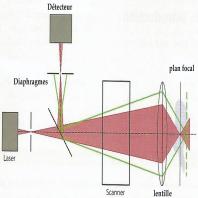

- eFig. 9-2 - Principe de la microscopie confocale (faisceau réfléchi en vert)

- eFig. 9-10 - Principe de fonctionnement de l'imagerie par optique adaptative